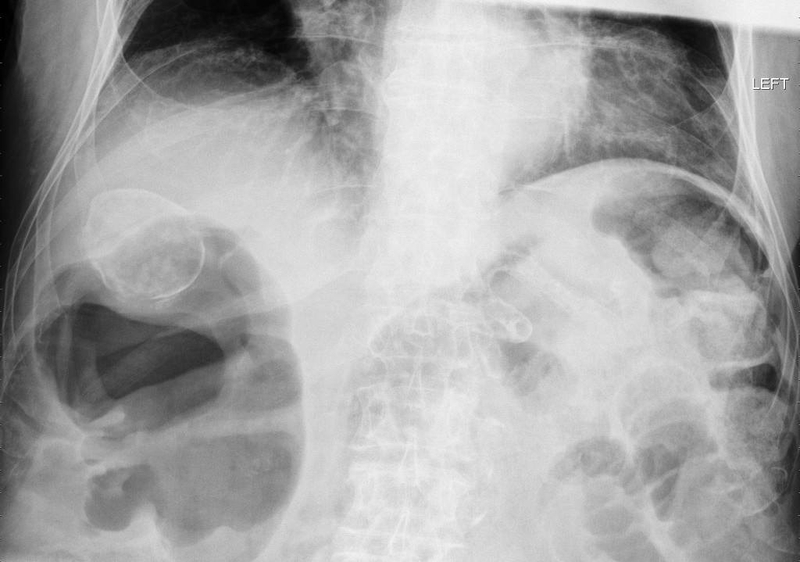

Túi mật sứ là trạng thái khi túi mật trở nên cứng, giòn và có màu xanh do quá trình vôi hóa. Bệnh này thường không tạo ra các triệu chứng cụ thể và thường chỉ được phát hiện ngẫu nhiên qua các hình ảnh như chụp X-quang bụng hoặc CT scan bụng. Ban đầu chỉ một phần của thành túi mật trở nên vôi hóa, kết dính vào niêm mạc. Sau đó, quá trình vôi hóa này có thể lan tỏa, thay thế toàn bộ mô của túi mật bằng canxi.

Chẩn đoán túi mật sứ đòi hỏi việc thực hiện các xét nghiệm hình ảnh để đưa ra kết luận chính xác. Dưới đây là các xét nghiệm phổ biến: